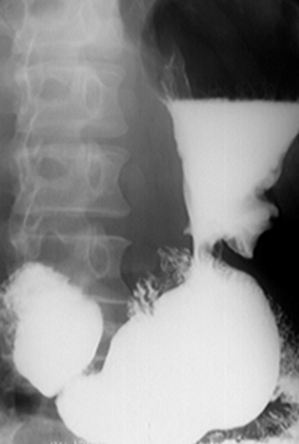

Hernie hiatală prin rostogolire